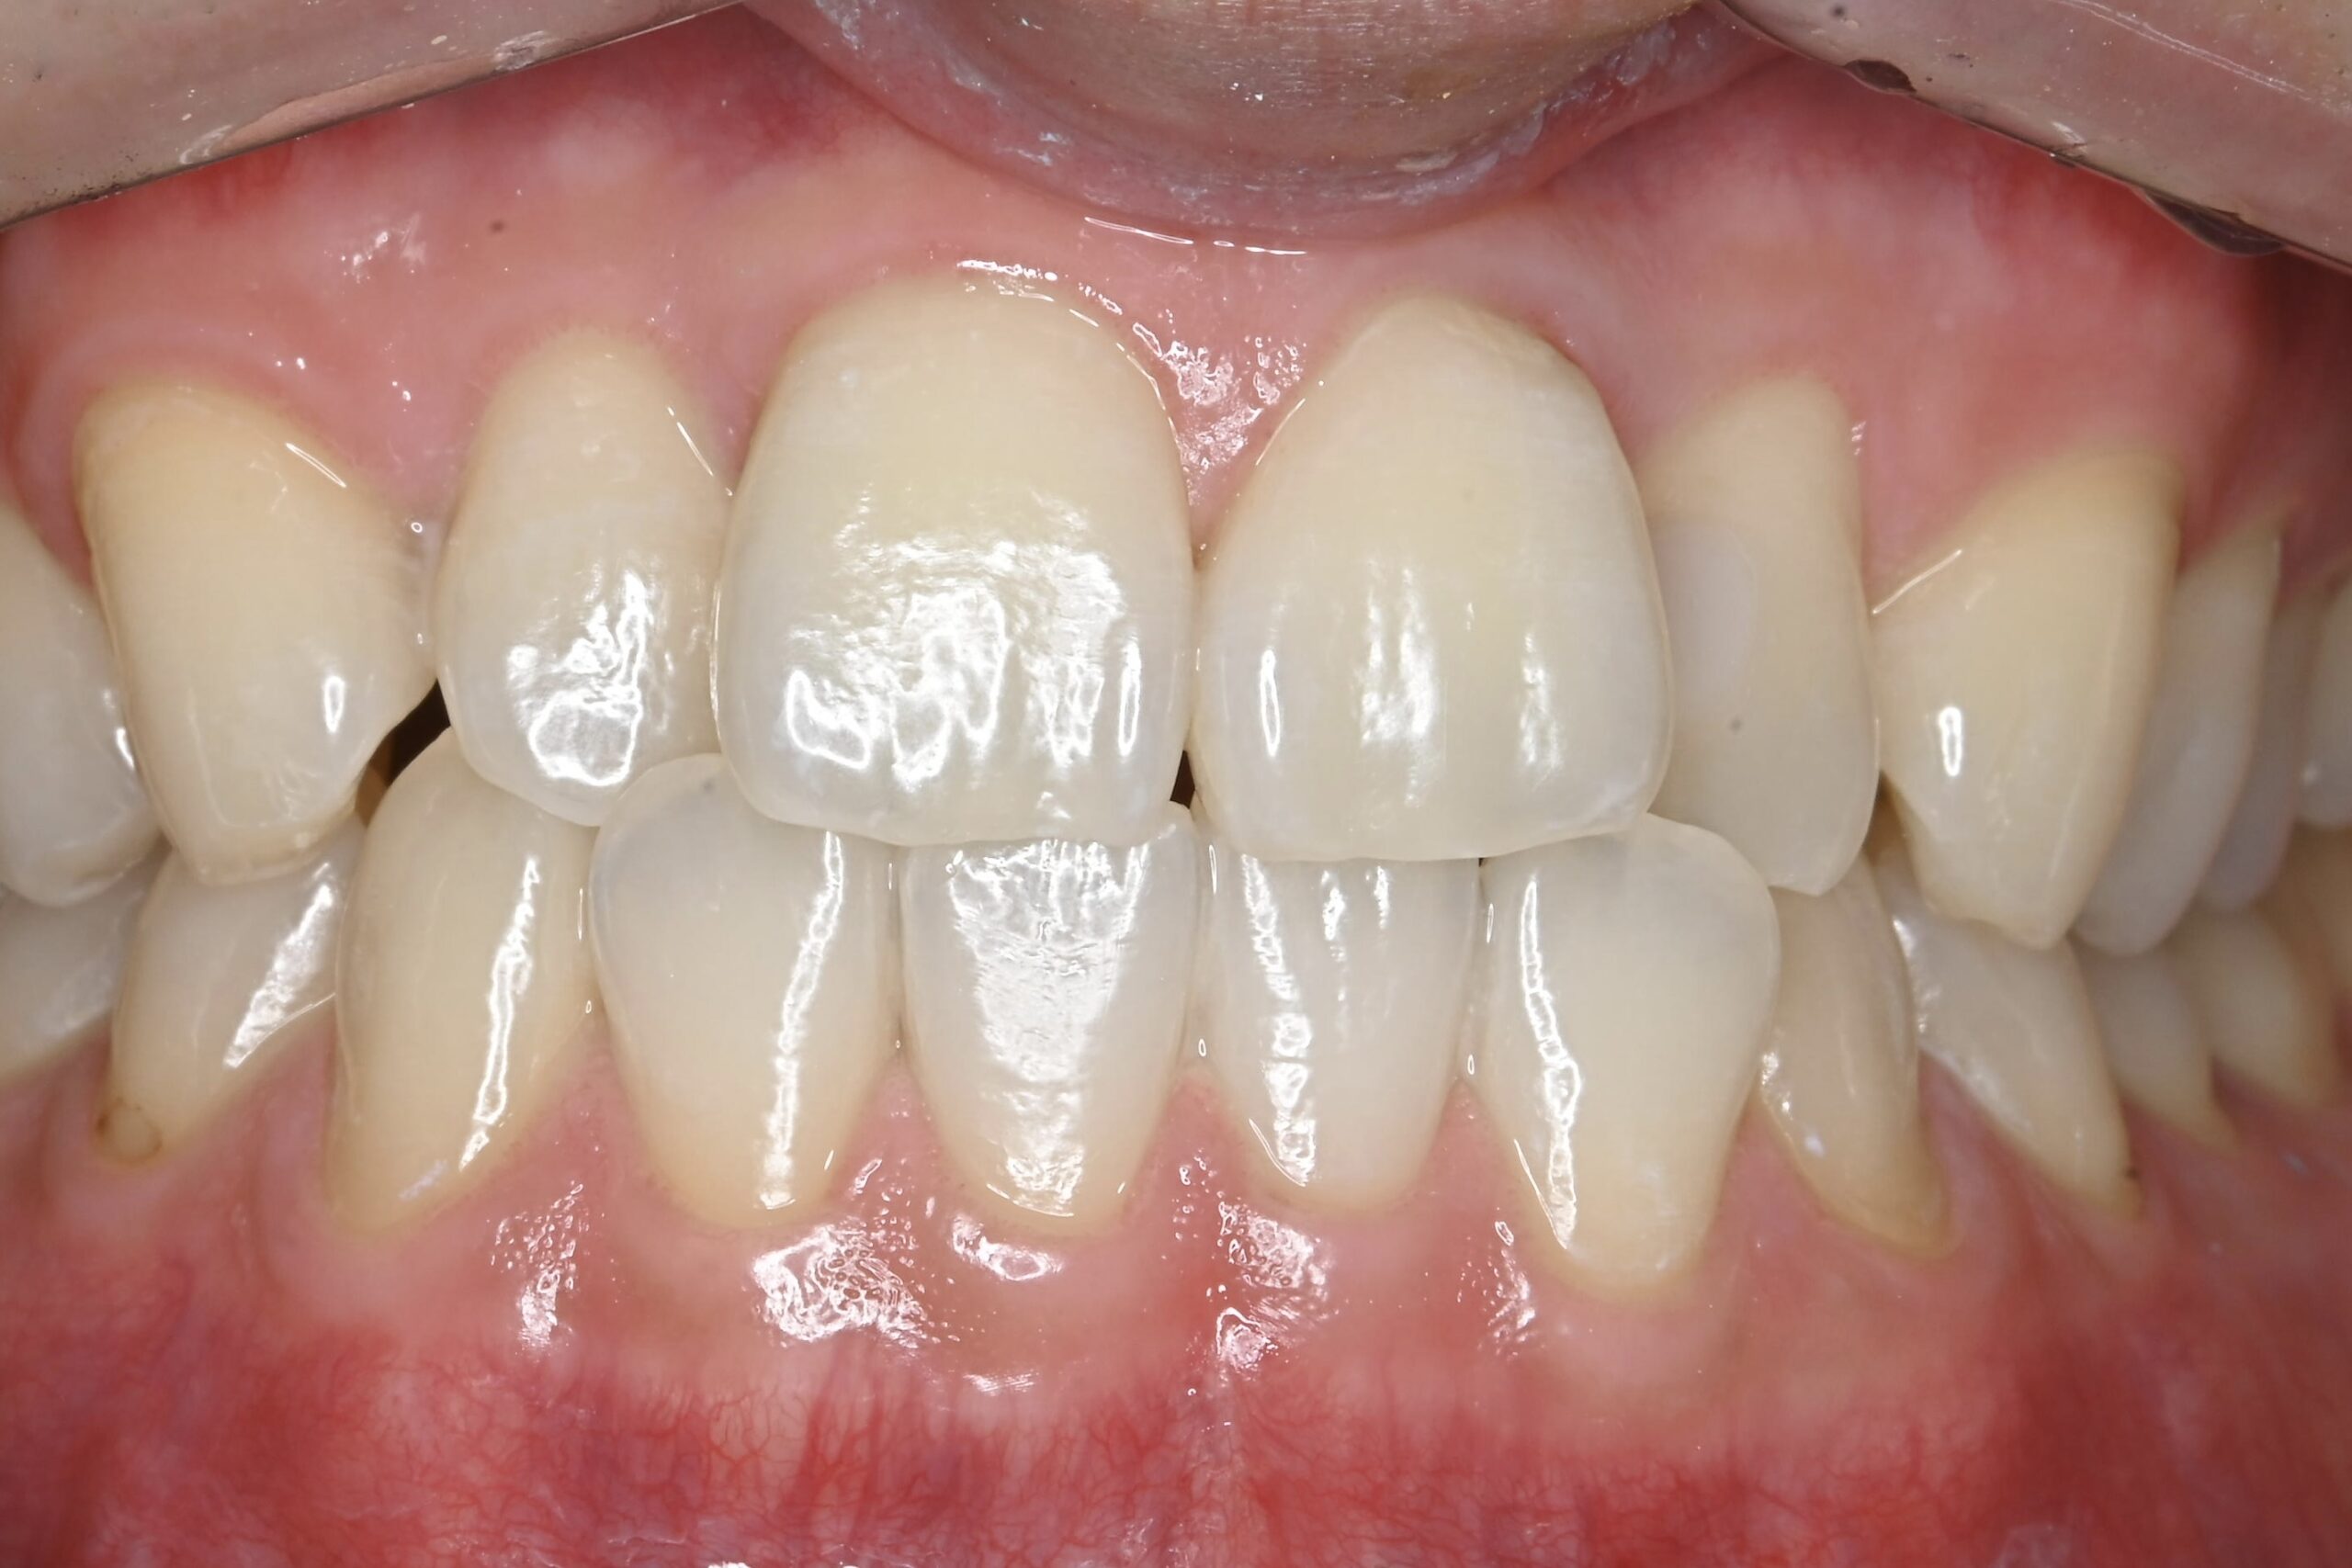

初診時

ブラッシング指導・スケーリング後

| 主訴 | 歯茎から出血する 歯科を受診するのは5年ぶり |

| 治療内容 | ブラッシング指導 歯肉縁上スケーリング(歯石の除去) 歯面清掃 |

| 治療期間 | 1ヶ月 |

| 費用 | 保険治療 |

| リスク・副作用 | 歯肉が引き締まることによる歯肉退縮 歯肉退縮による審美不良(歯が長く見える)や知覚過敏症状の発生 |